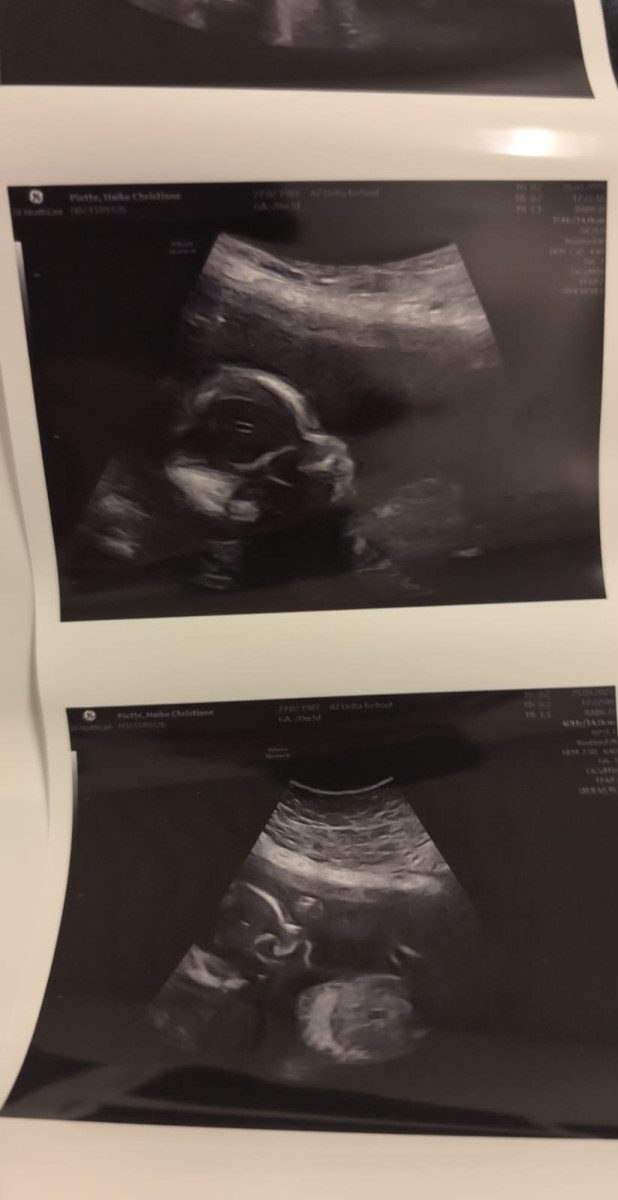

Toen we samen naar het scherm keken en de eerste beelden zagen van onze ongeboren dochter, werden we overspoeld door emoties. Daar was ze: klein, kwetsbaar, en al zo bijzonder. We zagen haar hartje kloppen en haar kleine lijfje bewegen. Wat ons vooral opviel, was hoe ze zich lekker had genesteld—ze lag heerlijk comfortabel, precies…